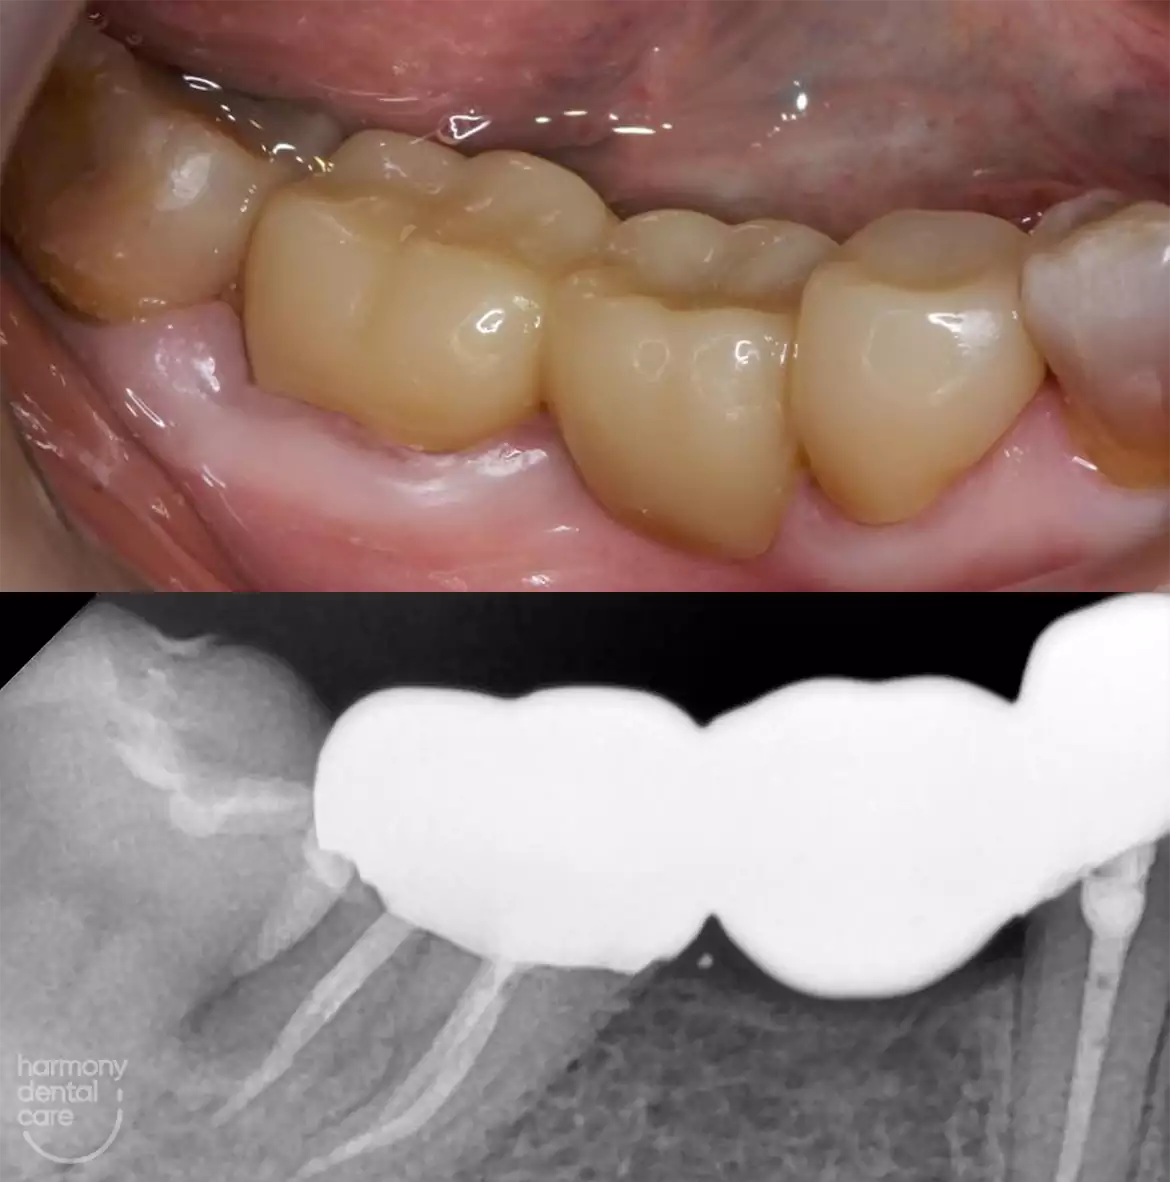

Smile gallery

Perubahan Nyata untuk Kesehatan Gigi Anda!

Dengan perawatan khusus di Harmony Dental, gigi Anda akan terlihat lebih bersih, rapi, dan terawat. Lihat perubahan sebelum dan sesudah yang membuktikan komitmen kami terhadap kesehatan mulut Anda.